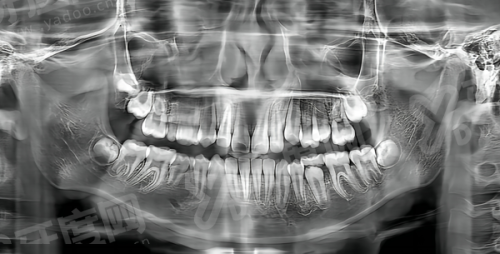

1. 正雅T1咬合诱导技术:主攻咬合诱导,核心是通过短期干预引导颌骨正常发育、调整咬合关系,主要适用于乳牙期(3岁起)、替牙早期或替牙中期孩子,解决牙弓狭窄、牙列不齐、地包天等咬合异常问题。

2. 正雅T2全周期矫正技术:属于全周期矫正,聚焦替牙晚期至恒牙列期的儿童及青少年,结合牙齿健康和颌面发育状况进行综合管理,目标是建立正常恒牙牙列关系及咬合关系,从更长期维度改善口腔健康。

1. T1侧重“早期干预纠正”:当孩子3岁起出现地包天、凸嘴、咬合不齐等问题时,可通过T1技术快速介入,利用3-6个月的周期引导颌骨发育,避免问题随年龄增长加重,减少成年后矫正难度。

2. T2侧重“全周期健康管理”:孩子进入替牙晚期后,骨骼和牙齿发育进入关键期,T2技术通过持续跟踪和调整,在生长发育黄金期进行干预,不仅改善牙齿不齐,还能优化颌面整体形态,适合需要长期维护牙颌面健康的青少年。